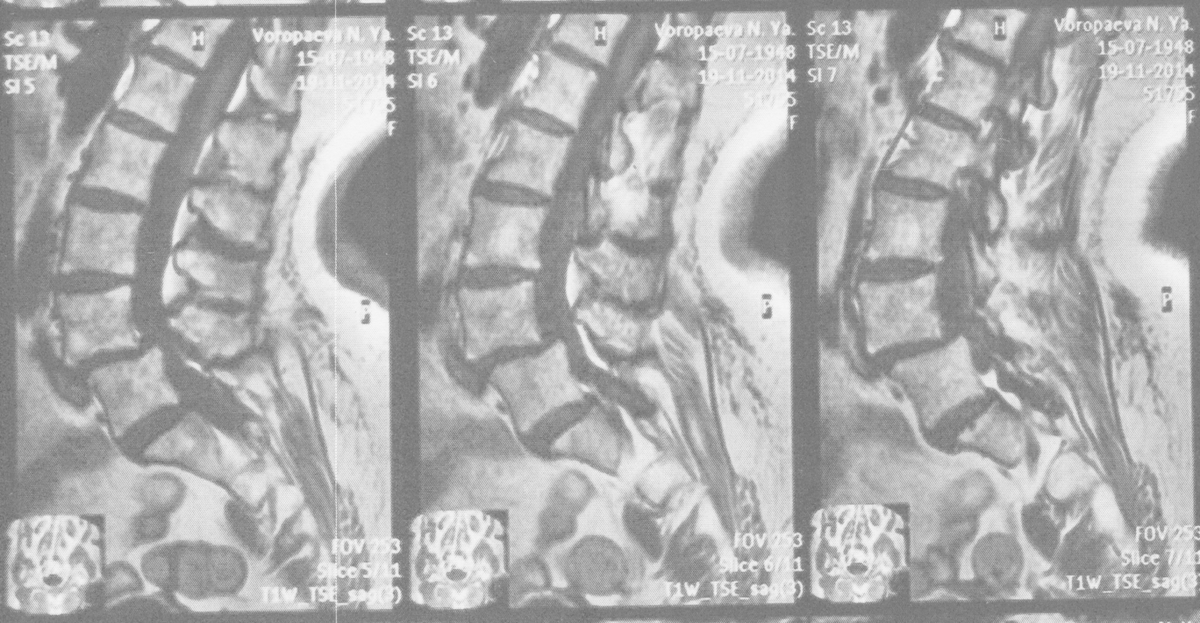

Снимок позвоночника с передним спондилолистезом ("антелистезом"). собственные наблюдения автора